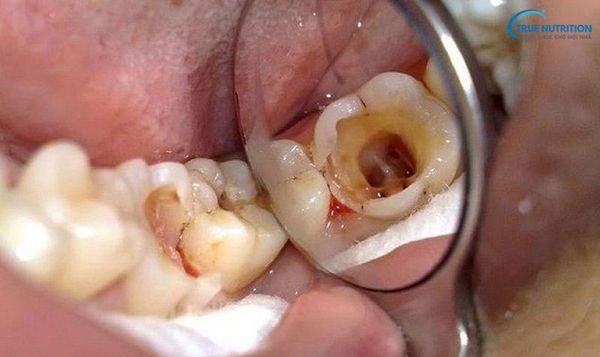

Giai đoạn 3: Vi khuẩn xâm nhập tủy răng

Khi tủy răng bị viêm nhiễm, răng trở nên đau nhức dữ dội. Nếu không điều trị, tủy có thể bị hoại tử, dẫn đến nhiễm trùng chân răng.

Giai đoạn 4: Răng vỡ hoàn toàn, chỉ còn chân răng

Ở giai đoạn cuối, thân răng bị phá hủy hoàn toàn, chỉ còn lại chân răng nằm trong xương hàm. Đây là hậu quả nghiêm trọng, gây mất chức năng nhai và ảnh hưởng xấu đến sức khỏe toàn thân.

- Nhiễm trùng và áp xe răng: Khi vi khuẩn tấn công vào tủy răng và chân răng, tình trạng nhiễm trùng xảy ra, gây đau nhức dữ dội và xuất hiện ổ mủ (áp xe).